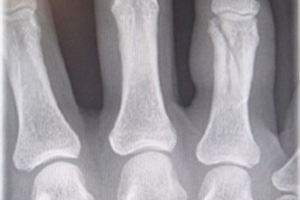

Therapie: Osteosynthese mit 2 Schrauben (s. Abb. 2)

Die Klägerin war gestürzt und hatte sich die rechte Hand verletzt. Die ärztliche Erstversorgung erfolgte am Unfalltag in der beklagten Klinik. In den Röntgenaufnahmen der rechten Hand wurde eine Mehrfragmentfraktur am Ringfingergrundglied diagnostiziert, die 10 Tage später offen reponiert und mit 2 Schrauben osteosynthetisch stabilisiert wurde.